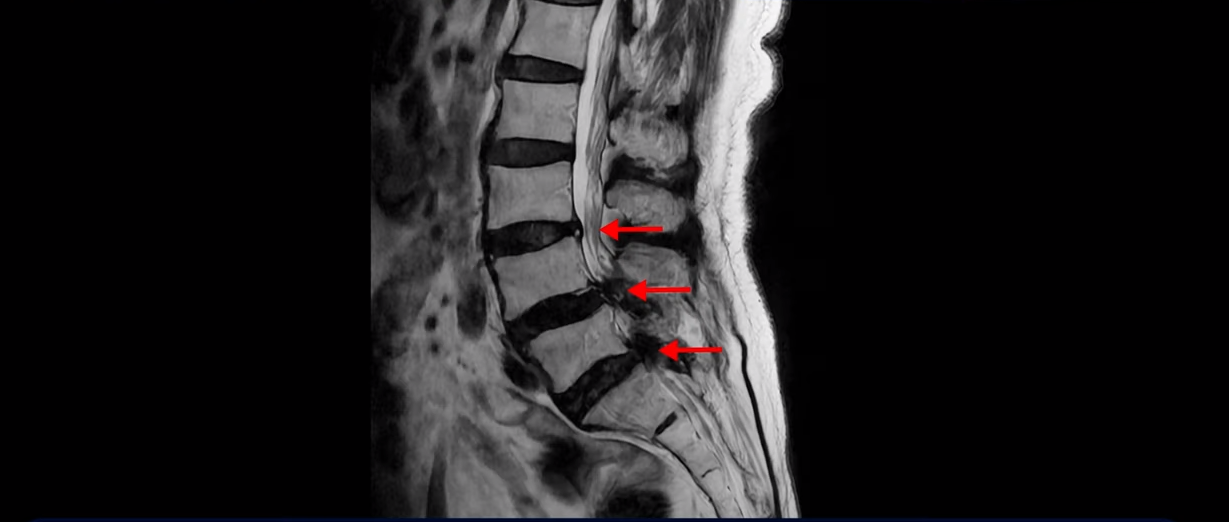

먼저 이분 MRI를 보면서 자세히 설명 드리겠습니다. 보시다시피 허리 여러 마디가 안 좋습니다.

특히 4번 5번에는 심한 중심성 협착이 있어 척추관이 매우 좁아져 있습니다.

5번 1번도 척추관이 좁아져 있고 특히 좌우 신경이 빠져나가는 추간공이 좁아져 있는데 5번 1번 왼쪽 추간공은 많이 좁아져서 신경이 눌리고 있습니다.

그런데도 아직도 많은 분들이 근육의 중요성을 모르고 신경치료만 하고 있습니다. 하지만 근육과 신경은 떼놓고 생각할 수가 없습니다. 근육이 나빠지면 신경 눌림이 심해져서 협착증 증상이 더 악화되고, 또 신경이 눌리면 근육도 더 빨리 나빠집니다. 반대로 근육이 좋아지면 신경 눌림이 줄어들고 협착증이 좋아집니다. 신경이 눌린다고 하니까 신경 눌림을 풀어주는 수술만 생각을 하시는 분들이 많은데 근육이 좋아져서 허리를 잘 지지해주면 신경이 덜 눌립니다. 이 환자분도 근육이 얼마나 안 좋은 지는 이분 척추가 얼마나 휘어있는 지만 봐도 알 수 있습니다. 보시다시피 근육들이 척추를 잘 지지하지 못하니까 척추가 심하게 휘어있습니다.